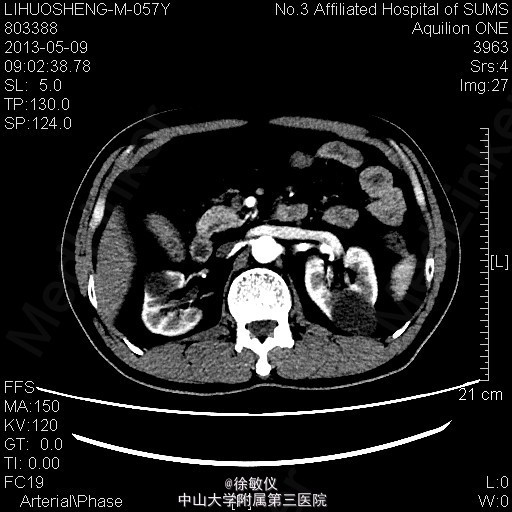

看图片,你的诊断是什么?

老年男性,发现血压升高1年余。平素有降压治疗,但血压控制欠佳,血压最高210/110mmHg,平时血压波动在160-190/90-110mmHg。